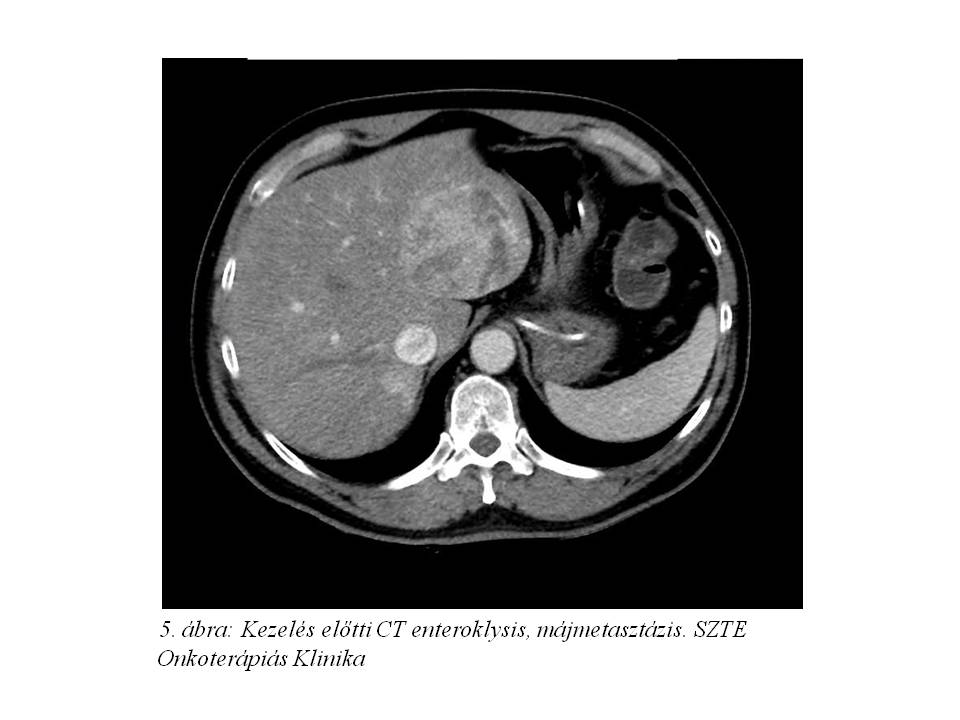

Tekintettel a diagnózis óta eltelt több hónapra re-staging hasi MR (4. ábra) és CT enteroklysis vizsgálat (5. ábra, 6. ábra, 7. ábra) történt. Az előbbi változatlan állapotot írt le, azonban az utóbbin a terminális ileum kezdeti szakaszán kb. 1,1x1,8x10 mm-es térszűkítő folyamat is ábrázolódott, mely megfelel a primer neuroendokrin tumornak.